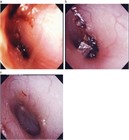

著者: 小川洋 福島県立医科大学会津医療センター 耳鼻咽喉科学講座

1. 慢性の外耳道炎、外耳道湿疹は全身的な皮膚疾患に伴うことがある。乾癬やアトピー性皮膚炎、接触性皮膚炎が原因となっているものに関しては問診、パッチテストが必要となる。

1. 急性限局性外耳道炎と急性乳様突起炎はどちらも外耳道が腫脹し耳介が変位することがあるが、起因菌の頻度が異なること、治療方針が異なることから鑑別が重要となる。

1. 通常急性外耳道炎の場合真菌感染の頻度は10%程度と低いが、これらは通常の治療に抵抗するため、このような場合には真菌感染を強く疑い、真菌に対する治療を行う。